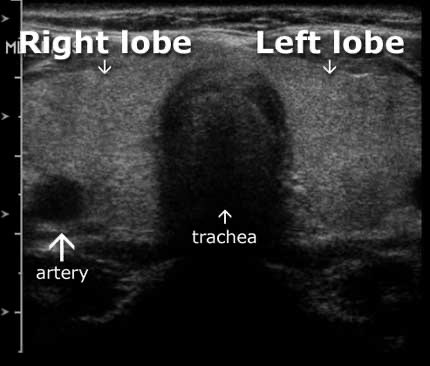

ماهي #عقيدات الغدة الدرقية ؟

هي عبارة عن نمو غير طبيعي للخلايا داخل #الغدة_الدرقية ينشأ منه بعض النتوءات والتكتلات.